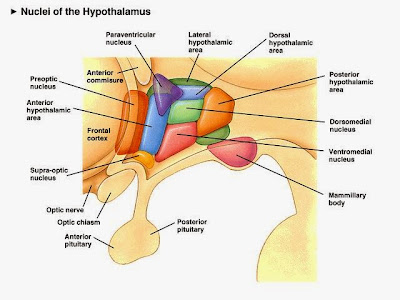

So what controls much of this neuroendocrine system? Your brain of course. Well, a small part of your brain that's pretty old in terms of evolution (even primitive hagfish have a pituitary). The hypothalamus senses many of the inputs that tell your brain just how well your body is maintaining homeostasis. If something goes astray, or if there is a change in your environment that forces a change in your body chemistry, the hypothalamus will then spring into action (O.K., it’s always working, it will just work harder).

The hypothalamushas a neuroendocrine relationship with the pituitary gland (better named the hypophysis, where hypo = under and physis = growth – it is a growth under the brain). The hypophysis comes in two parts. Both parts release hormones, but where those hormones come from and the sources of the tissues of the two pituitary parts are very different.

The anterior pituitary isn’t part of the brain at all. The tissue for the adenohypophysis(anterior pituitary, adeno = secreting) comes from the roof of the embryonic mouth. It is epithelial in origin and has cells that produce hormones in response to signals from the hypothalamus (also hormones). Here’s how it happens.

Well, it gets worse. There are six releasing hormones from the hypothalamus that stimulate production and release of seven hormones from the adenohypophysis that then act on at least 20 endocrine glands and neuroendocrine cell types. Hypothalamus to adenohypohysis to endocrine gland – it’s called an axis, and there are several of them.

On the other hand, the posterior pituitary (neurohypohysis) is derived from brain tissue. Instead of the neurons of the hypothalamus producing releasing hormones that then act on the neurohypophysis, the hypothalamic neurons project right into the posterior pituitary where they deposit their hormones (oxytocin and antidiuretic hormone). The neurohypophysis doesn’t make any hormones itself, it just stores what the hypothalamic neurons produce and then releases them to the circulatory system.